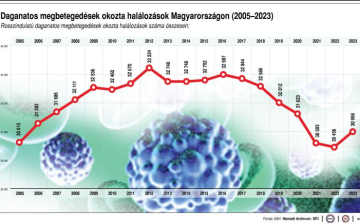

Szerbiai orvosok szerint a NATO légicsapásainak következményeként sok a rákos megbetegedés az országban

A Jugoszlávia elleni 1999-es NATO-légicsapások következtében az utóbbi 25 évben jelentősen megnőtt a rákos megbetegedések száma - állítják szerbiai orvosok.

Rákellenes nap - A fiatalabb nők körében emelkedett a daganatos megbetegedések száma

A Magyar Rákellenes Liga neves szakemberek előadásaival várja az érdeklődőket, és kifejezetten a fiatal nők körében megnövekedett esetszámra is fel kívánja hívni a figyelmet a rákellenes napon.